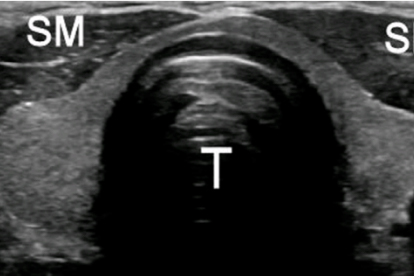

山东省立医院是山东省规模大的综合性医院之一,内分泌科在甲状腺疾病诊疗方面具有显著优势。医院拥有的超声诊断设备和细针穿刺技术,能够对甲状腺囊肿进行评估。内分泌科团队在甲状腺囊肿的微创治疗方面积累了丰富经验,开展超声引导下硬化治疗等特色技术。